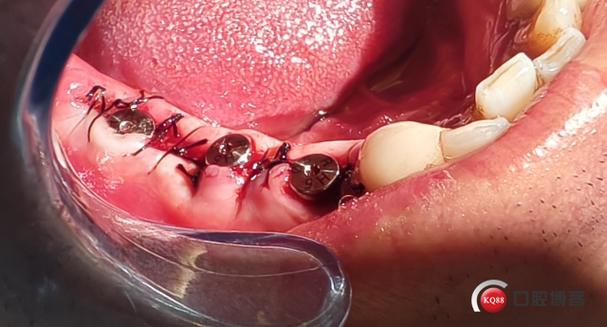

(图片来源网络,侵删)- 初期稳定性要求高: 种植体在新鲜拔牙窝内必须获得良好的初期稳定性,否则容易失败。